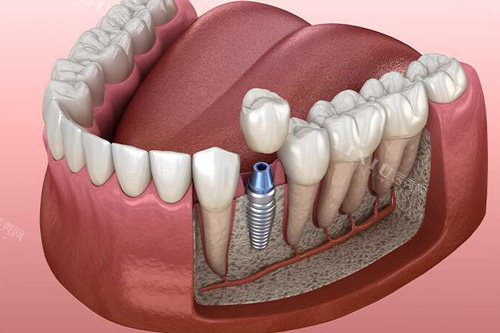

假体的使用寿命受材质特性影响显著,不同材质在生物相容性、力学性能、耐腐蚀性及抗疲劳性等方面的差异,会直接决定其在体内的长期稳定性和功能维持时间。金属材质中,钛及钛合金因具备优异的生物相容性,成为骨科和牙科的首要选择材料。此外,氮化硅作为牙科种植体材料,断裂韧性高,抗压强度与人体骨相似,可以满足种植体的基本力学要求,具有良好的生物相容性。

种植牙的结果通常是比较理想的,作为一种牙齿修复方法,种植牙因其稳定性和舒适性受到许多患者的青睐。它能够比较好地模拟自然牙齿的功能,并且与牙槽骨紧密结合,减少对邻牙的损害。种植牙具有较高的稳定性和承重能力,能够更好地模拟自然牙齿的功能。同时,种植牙不需要磨损邻牙,对周围牙齿保护较好。

种植牙的结果通常是比较好的,能够修复牙齿功能和美观。种植牙通过在牙槽骨内植入人工牙根,与自然牙齿相似,具有较高的稳定性和耐用性。因此,无论选择哪个品牌,关键在于确保种植体与患者的口腔状况相匹配,并由经验充足的医生进行手术。